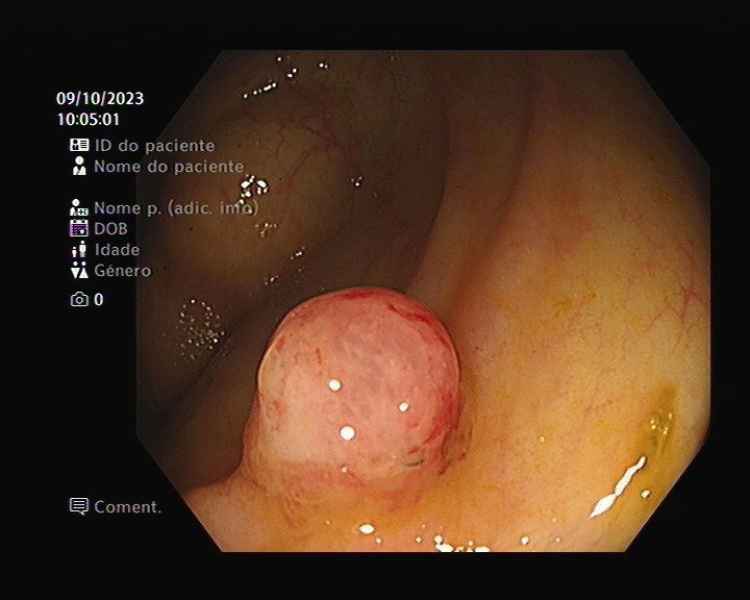

An umbilical cord-like polyp

Fotografia